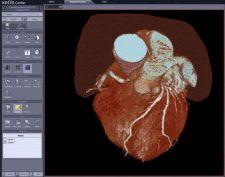

INFINITT North America's Xelis Cardiac software tool uses 3D volume rendering and other post-processing techniques to improve visualization and analysis of coronary vessels.

INFINITT developed the Xelis line of products as software modules that provide accelerated data loading and clinical tools for enhanced viewing of large-volume data sets. Xelis-Cardiac’s Vessel Analysis package includes one-click auto vessel tracing, MPR-view, Angio-emulation view, segmentation functions, automatic ribcage removal, C-CPR (compare curved planar reformation), stenosis and soft plaque analysis, and automatic calcium scoring.

Xelis Cardiac solution improves utilization of multi-slice CT data and improves radiologists, productivity, the company said.